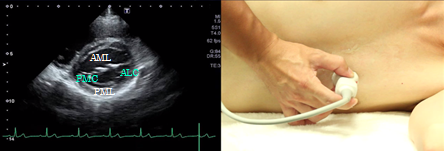

Mitral orifice level

The mitral orifice level of the short axis view of the left ventricle depicts the mitral valve with a large anterior cusp in the front and a small and wide posterior cusp at the backside of the image. The anterior commissure is located on the right side of the screen and the posterior commissure on the left side. This view is used to determine the site of mitral valve prolapse and measure the mitral valve area in case of mitral valve stenosis.